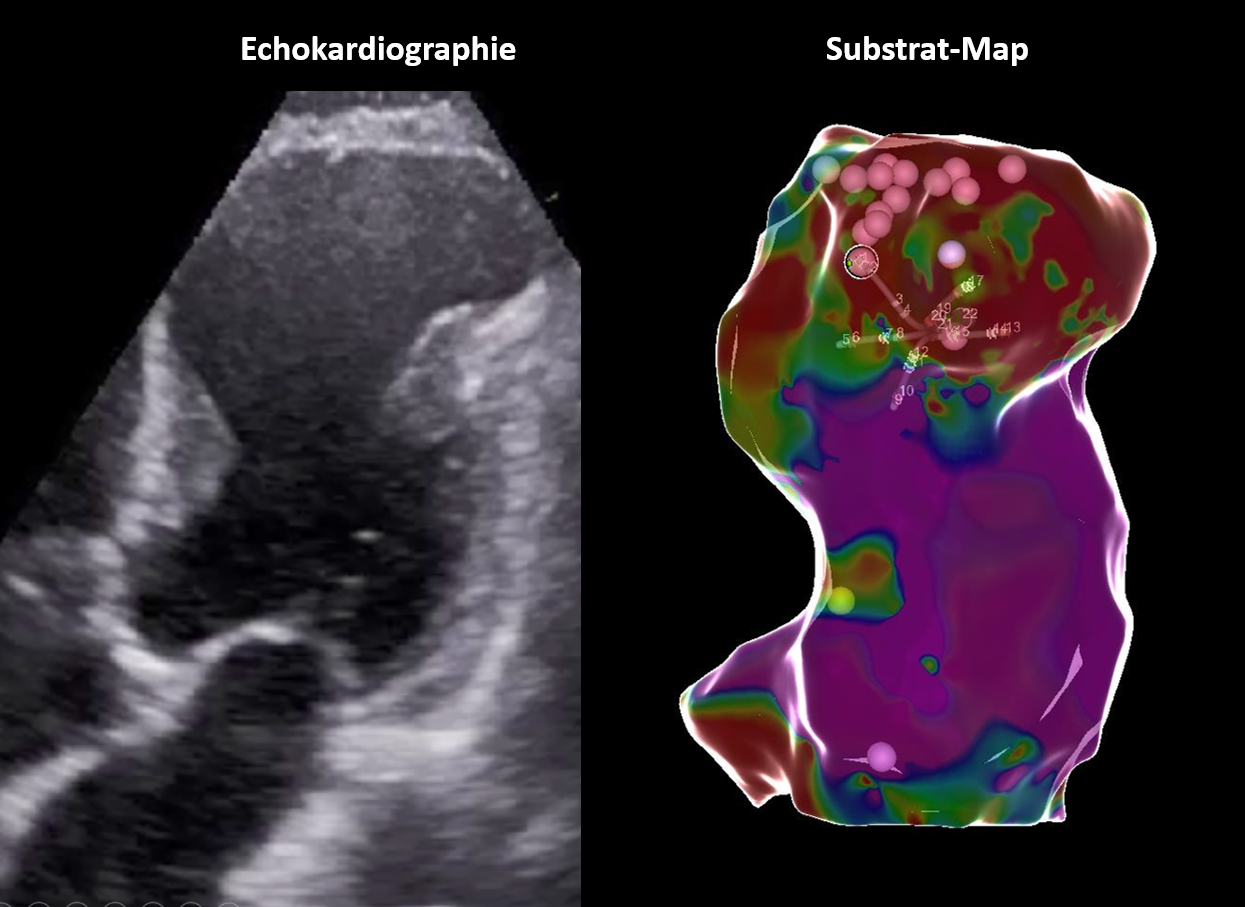

Links ein Echokardiogramm eines Herzens, rechts eine Substrat-Karte mit farbiger Visualisierung und Markierungen.

Komplexe Ventrikuläre Herzrhythmusstörungen

Auch die Behandlung komplexer Herzrhythmusstörungen aus den Herzkammern gehört zu unserem Leistungsportfolio.

Angefangen bei gutartigen, aber symptomatischen oder sehr häufigen Extraschlägen bei sonst herzgesunden Patienten, bis hin zur Katheter-Behandlung akut lebensbedrohlicher anhaltender ventrikulärer Tachykardien - dank modernster Navigationstechnik und hoher Erfahrung sind auch komplexe Eingriffe mit hoher Erfolgsaussicht möglich.